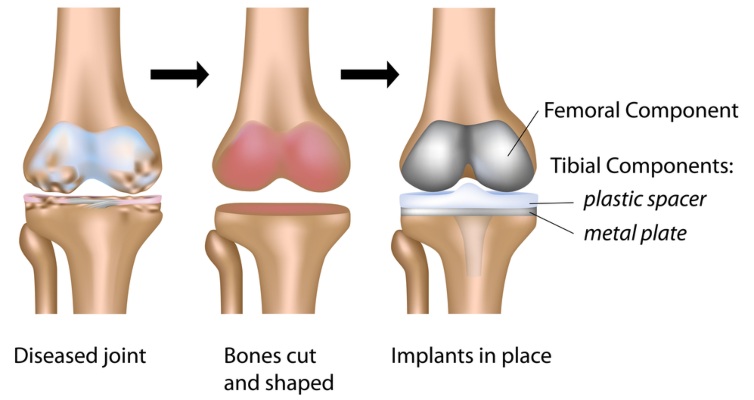

Total knee replacement surgery involves replacing parts of the knee joint which are damaged, arthritic or diseased with artificial metal and plastic components (known as a prosthesis). The prothesis enables the knee joint to move naturally.

Every knee is unique, and Dr Riazi selects from a range of implant sizes to ensure the best fit. A tourniquet is placed around the upper thigh to reduce blood loss. Pre-operative planning includes advanced 3-D modelling or computer-assisted navigation, allowing precise alignment of the knee replacement for optimal function and long-term results.

Once the optimal fit is confirmed, Dr Riazi implants the final prosthesis, with or without bone cement. He checks that the knee moves smoothly and is properly aligned before closing the incision with dissolvable sutures and applying a dressing.